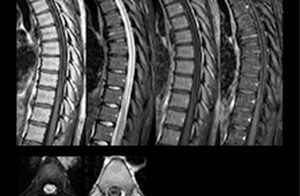

“For the thoracic and cervical spine routine non-contrast exam, for example, we perform one mDIXON T2 TSE sequence, which provides us with two outputs: the fat-and-water-together T2-weighted images, as well as the water-only sagittal T2-weighted images. And then we also perform an axial gradient echo exam.”

Cervical spine routine exam

This patient presented with headache that was worse with neck flexion and we see a Chiari 1 malformation with low-lying cerebellar tonsils as well as some degenerative cervical thrombolytic change.